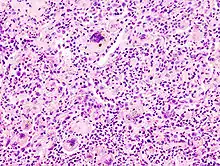

Histopathologic image of aspiration pneumonia in an elderly patient with debilitating neurologic illness. Note foreign-body giant cell reaction. Autopsy case. H & E stain.

A foreign-body giant cell is a collection of fused macrophages (giant cell) which are generated in response to the presence of a large foreign body. This is particularly evident with catheters, parasites, or biomaterials that are inserted into the body for replacement or regeneration of diseased or damaged tissues.[1][2] Foreign body giant cells are also produced to digest foreign material that is too large for phagocytosis.[3] The inflammatory process that creates these cells often leads to a foreign body granuloma.